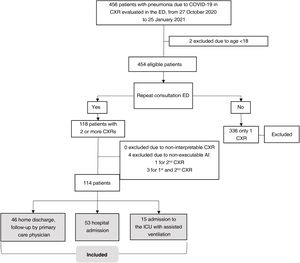

Setting and sample selectionThe selection criteria were: a) patients ≥18 years old; b) positive reverse transcription polymerase chain reaction (RT-PCR) or antigen test for SARS-CoV-2 infection; c) unfavorable respiratory evaluation and initial CXR (CXR1) with pulmonary opacities, probable or indeterminate findings of COVID-19 pneumonia10; d) without criteria making hospital admission necessary at the time of CXR1 (no dyspnoea, respiratory rate <22, oxygen saturation ≥95%, Brixia score <14 and without risk of progression taking into account concomitant diseases); e) and who require a second consultation and a new CXR (CXR2) due to an unfavorable clinical evolution at home during the month after the first CXR (Fig. 1).

Sample selection with inclusion and exclusion criteria.

(1) Pneumonia on chest X-ray: pulmonary opacities, probable or indeterminate findings of COVID-19 pneumonia.

(2) Hospitalisation criteria:

Main criteria:

-Dyspnoea.

-Respiratory rate ≥22.

-Basal O2 saturation < 94%.

Additional criteria to take into account:

-Brixia score on chest X-ray:

-0–4: low-risk patient.

-5–13: the need for admission must be correlated with the clinical and historical history.

-14–18: high-risk patient.

-Patients at high risk according to concomitant diseases.

AI-CXR: CXR processed with the AI tool; CXR: chest x-ray; RT-PCR: real-time reverse transcription polymerase chain reaction.

Patients were excluded if radiological images were non-diagnostic due to poor technical quality or if AI-CXR images were not available (Fig. 1).

ResultsSampleOutpatients with COVID-19 considered eligible were included consecutively from 27 October 2020 to 25 January 2021. The initial sample comprised 118 patients with CXR1 and CXR2. Four patients were excluded because AI-CXR images could not be obtained for technical reasons. In total, 114 patients were included (57.4±14.2; 65 men), 53 (46.5%) required hospital admission and 15 (13.2%) required assisted ventilation in the ICU (Fig. 3). The characteristics of the sample are shown in Table 1.